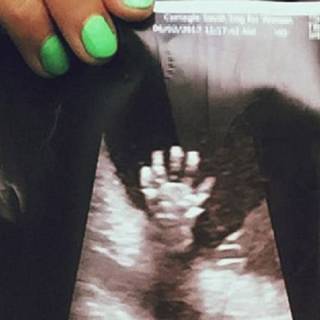

NEW YORK – Una coppia di genitori in attesa del loro secondo figlio sono rimasti sorpresi quando hanno visto la scansione della radiografia fatta alla mamma, alla ventesima settimana di parto. All’interno del grembo materno, il piccolo nato sembra dare loro il “cinque”. Libby e Mathew Vlasic di New York sono rimasti colpiti e soprattutto felicissimi di sapere che Miles, il loro figlio di sei anni, avrà una sorellina che sta crescendo proprio bene. Lo dimostra anche la foto che i genitori hanno deciso di condividere facendola diventare virale in poco tempo.

La scansione è stata fatta alla ventesima settimana. La coppia è rimasta favorevolmente sorpresa nel vedere la piccola che dà il “cinque”. Libby, al Daily Mail ha raccontato: “Ci sono voluti parecchi anni di tentativi per avere un secondo figlio. E’ stata una lotta. Avevo abbandonato molto la speranza di avere un secondo bambino, ma la vita lavora in modi misteriosi e mi sono miracolosamente trovata di nuovo incinta. Nel giorno della scansione, non mi sentivo molto bene fisicamente, quindi mi ci sono voluti un po ‘di minuti per capire cosa stesse successo. Poi, il tecnico di scansione era molto entusiasta di quello che aveva visto a livello medico. Mi ha consegnato la foto e mi sono resa conto di quanto fosse speciale la mia bambina”.

Libby, che ora ha 30 settimane di gravidanza, ha raccontato di aver condiviso la foto su profili dedicati, su Instagram, proprio alla gravidanza, scoprendo che, in pochi giorni aveva superato le 6000 condivisioni.